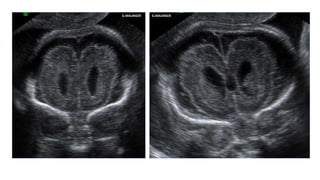

TRANSTORNOS DE PROLIFERACIÓN: MACROCEFALIA

28ss

TRANSTORNOS DE PROLIFERACIÓN:MACROCEFALIA • Head circumference above the 98th percentile or more than 2 standard deviations above the mean. • Macrocephaly is relatively frequent in children and adults and is a common cause for genetic consultation. • The diagnosis assumes that other obvious causes of head enlargement, such as hydrocephalus and cerebral tumors, have been excluded. Usually, macrocephaly is familial and benign and frequently it manifests only late in pregnancy or after delivery.

• 20.